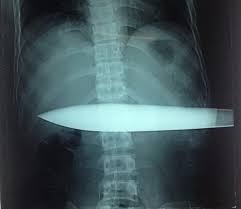

Ảnh minh họa. |